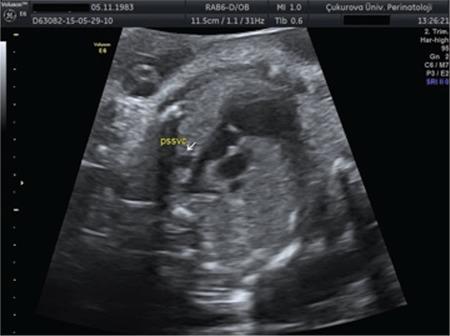

To evaluate persistent left superior vena cava (PLSVC) cases according to associated cardiac, extracardiac, and chromosomal anomalies in the prenatal period and to review their outcomes.

The data of patients with a prenatal diagnosis of PLSVC between January 2013 and December 2017 were reviewed retrospectively.

Data of 32 cases were reviewed. Nineteen (60%) cases were associated with cardiac defects, 5 (15%) were associated with both cardiac and extracardiac defects, and 8 (25%) had no associated anomalies. Two fetuses had karyotype anomalies. All patients with isolated PLSVC survived. Among the cases associated with extracardiac anomalies, cardiac anomalies, and with both extracardiac and cardiac anomalies, the survival rate was 40%, 40%, and 25%, respectively. Outcome was more favorable in cases with isolated PLSVC (100% vs. 40%).

Prenatally diagnosed PLSVC is associated with cardiac and extracardiac anomalies in the majority of cases. The prognosis is good in isolated cases, but worsens when accompanied by cardiac or extracardiac anomalies.